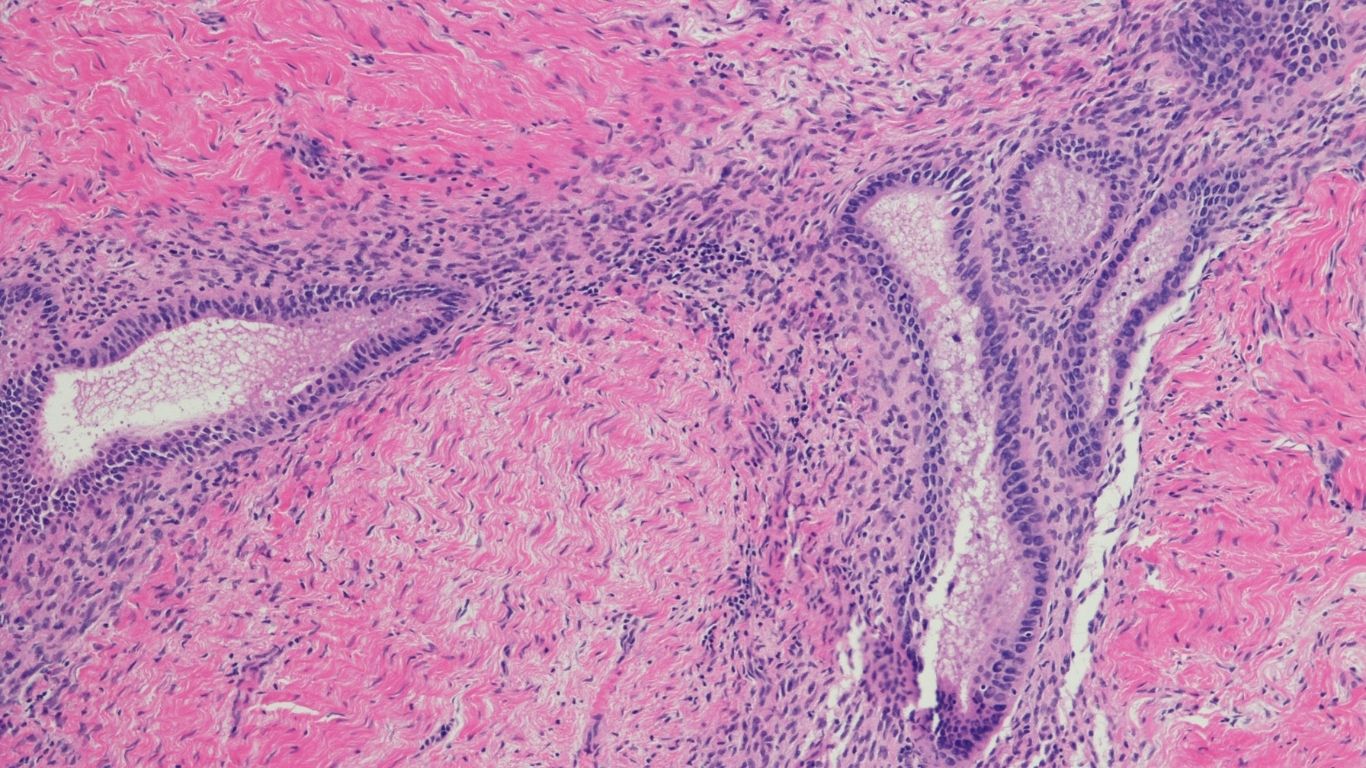

L’endométriose est une maladie inflammatoire chronique qui touche environ 1 femme sur 10 en âge de procréer. Elle se caractérise par la présence anormale de tissu endométrial (endomètre) en dehors de l’utérus (ovaires, trompes, vessie, intestin..)

Sous l’influence des hormones, ces tissus réagissent comme la muqueuse utérine normale, ils s’épaississent, saignent mais ne peuvent pas s’évacuer ce qui entraîne une inflammation chronique, des douleurs, des adhérences et parfois une infertilité.